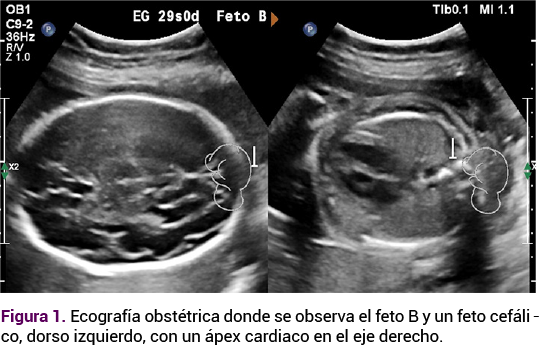

Debido a las altas tasas de complicaciones en los embarazos gemelares se indicó un control ecográfico estricto. El Doppler fetoplacentario y la ecografía obstétrica de la semana 29 no mostraron alteraciones hemodinámicas; sin embargo, en el feto B se observó un ápex cardiaco y estómago de lado derecho (Figura 1), hallazgos sugerentes de situs inversus totalis. En el feto A no se documentaron alteraciones de lateralidad, ni otras malformaciones anatómicas asociadas.

<strong>Figura 1</strong>

Figura 1.